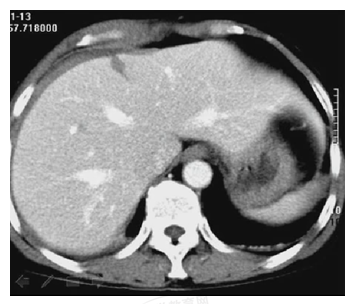

患者,女性,20岁。胸腹部被车撞伤5小时。诊断为

A.肝破裂

B.脾破裂

C.肝脾破裂

D.肝肾挫裂伤

E.肾损伤

【答案】A